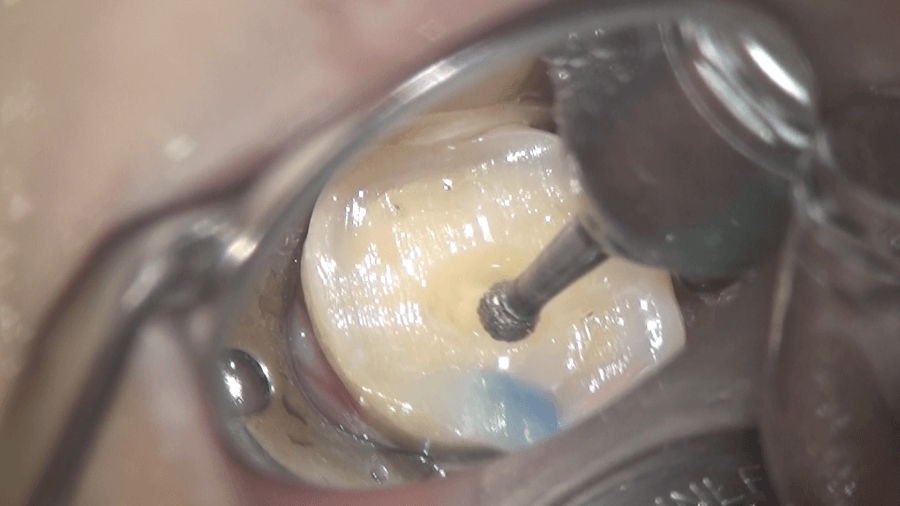

まず虫歯を取り除き、その部分をコンポジットレジンで充填し、その後、ラバーダムをして、歯の内部にアプローチしていきます。

まず、歯に穴を開けます。